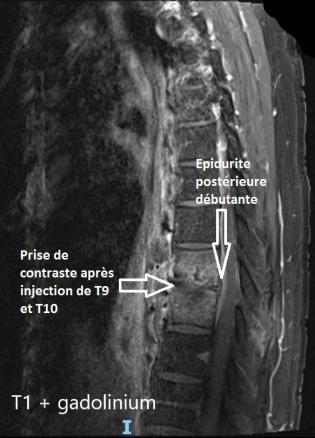

Spondylodiscite, abcès prévertébral antérieur, épidurite postérieure

IRM rachidienne, coupe sagittales, séquence T1 + gadolinium